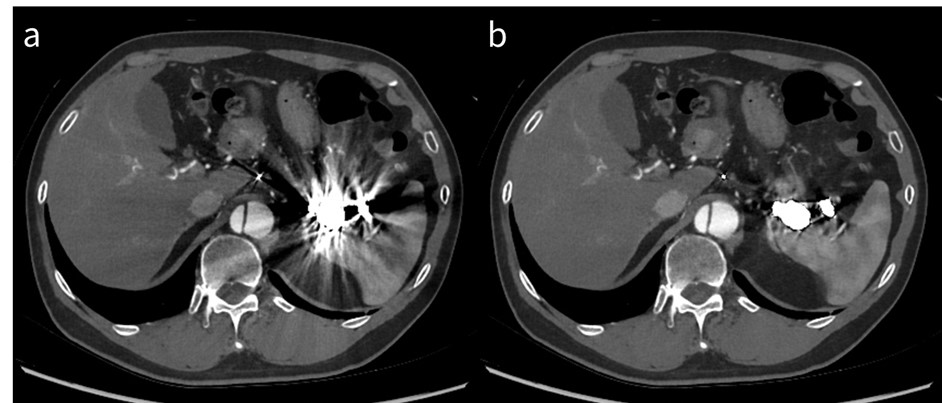

RevolutionApexElite_Gifu02_04.jpg

図3 高keV画像によるアーチファクト低減

a: 70 keV仮想単色X線画像

b: 140 keV仮想単色X線画像

腰椎術後状態であり金属アーチファクトが著明であるが、

140 keV仮想単色X線画像は70 keVと比較してアーチファクトが低減されている。